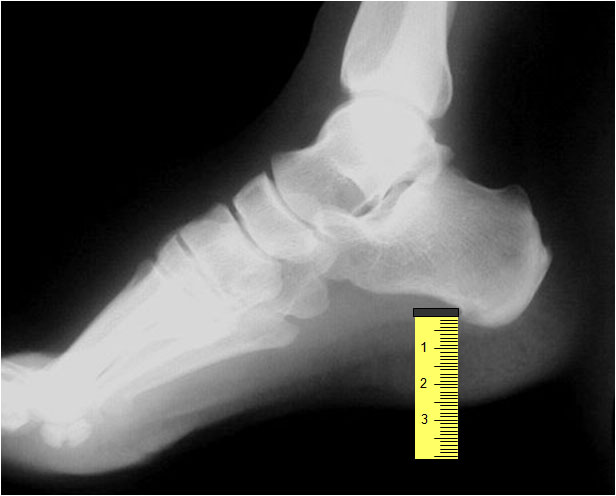

SIGNO DE LA LÁGRIMA

Signo de derrame articular en el tobillo, en la proyección lateral. Se manifiesta como una densidad de partes blandas en forma de lágrima (flecha), situada por delante de la articulación, que desplaza y deforma la almohadilla adiposa preastragalina.

Dodge, JP. The ankle teardrop sign. Radiology 2004; 231: 789-790.

http://www.gentili.net/signs/41.htm